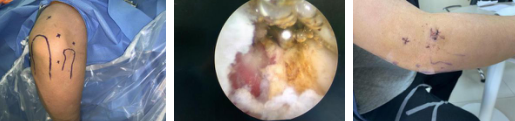

术前(左图)关节镜探查(中图)术后(右图)

本例患者网球肘病史半年以上,用了封闭、按摩、冲击波等治疗方式,病情均不见好转。后在家人的介绍下,找到sararz手外科的肘关节镜专家胡俊生。关节镜手术切口不到1公分,且只需打2-3个钉眼,对人体的创伤非常小。